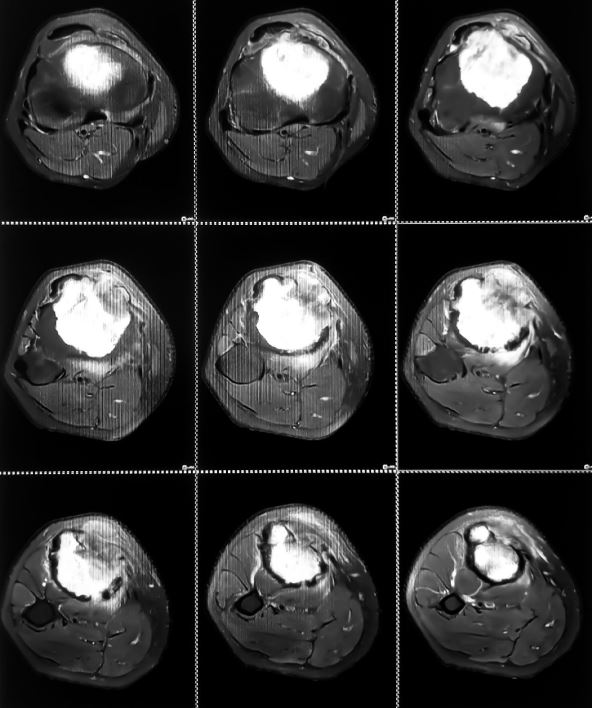

Tamo je konačno dobila odgovor koji je godinama tražila: uzrok bola nije bio išijas, već Evingov sarkom - retki i agresivni oblik raka kostiju koji pogađa isključivo mlade do 25 godina.

Evingov sarkom je retka i agresivna forma raka kostiju, koja se najčešće javlja kod dece, tinejdžera i mladih do 25 godina.

Najčešće zahvata karlicu, butnu kost, rebra ili kičmu, a simptomi uključuju:

Zbog sličnosti sa simptomima išijasa ili sportskih povreda, dijagnoza se često postavlja kasno. Lečenje je intenzivno i obuhvata hemoterapiju, zračenje i operaciju. Prognoza zavisi od stadijuma bolesti i brzine otkrivanja, zato je važno reagovati na svaki neobjašnjivi bol u kostima ili otok.